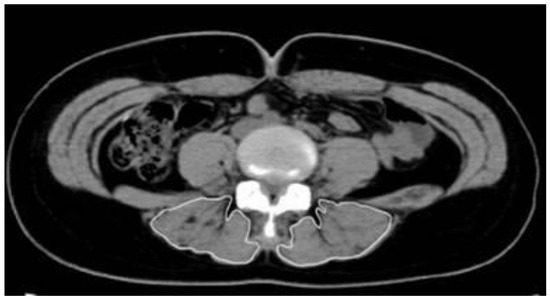

2.2.3. Cross-Sectional Area

Computed tomography (Sytec-Sri, GE, Boston, MA, USA) was performed to measure the CSA of the lumbar muscles. The test was conducted by a single radiologist with more than 20 years of experience who performed all imaging and measurements. On the monitor screen of the picture archiving and communication system, the range of CSA of the erector spinae muscle was analyzed, and the CSA (cm2) was subsequently calculated (Figure 1).

Figure 1.

Measurement of the cross-sectional area of the erector spinae muscles.